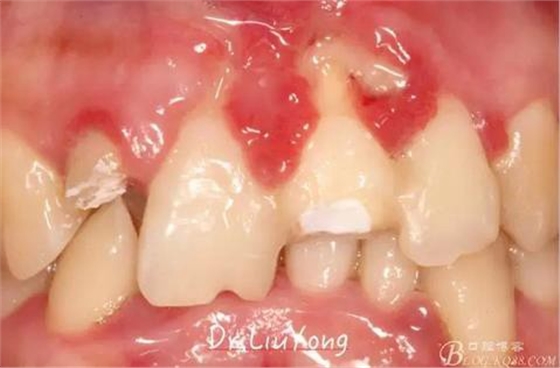

在松動牙固定的同時,嘗試保留B1唇側(cè)折裂牙槽骨塊,拆除縫線后,局部沖洗,牙周塞治劑覆蓋并固定游離骨塊。囑患者加強(qiáng)口腔衛(wèi)生,氯己定漱口液含漱,兩周后復(fù)查。兩周后拆除塞治劑,骨塊仍為游離活動狀態(tài),去除游離骨塊,局部沖洗上藥。

骨塊固定兩周后復(fù)查,如上圖